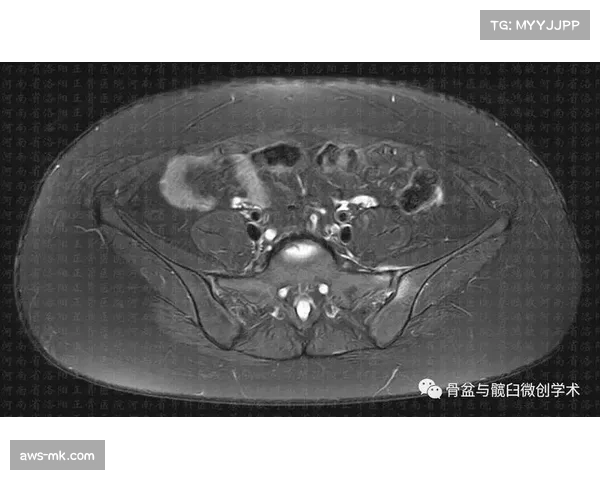

马莱莱的慢性劳损性耻骨炎并非一朝一夕所致,而是多次过度负荷和反复运动造成的伤病累积。耻骨炎是一种由于长时间过度运动或不当的训练导致的骨骼与肌腱的劳损,尤其是在职业足球中,频繁的高强度对抗、跳跃及快速改变方向等动作,容易引发此类伤病。

这一疾病的典型症状包括耻骨区域的疼痛、活动受限以及运动过程中加剧的疼痛。马莱莱的具体症状是上半身负荷较大时,尤其是在进行跑动、射门和拦截等动作时,耻骨部位的疼痛愈发剧烈,影响了他的比赛状态与发挥。这也是导致他不得不暂停比赛和进行治疗的主要原因。